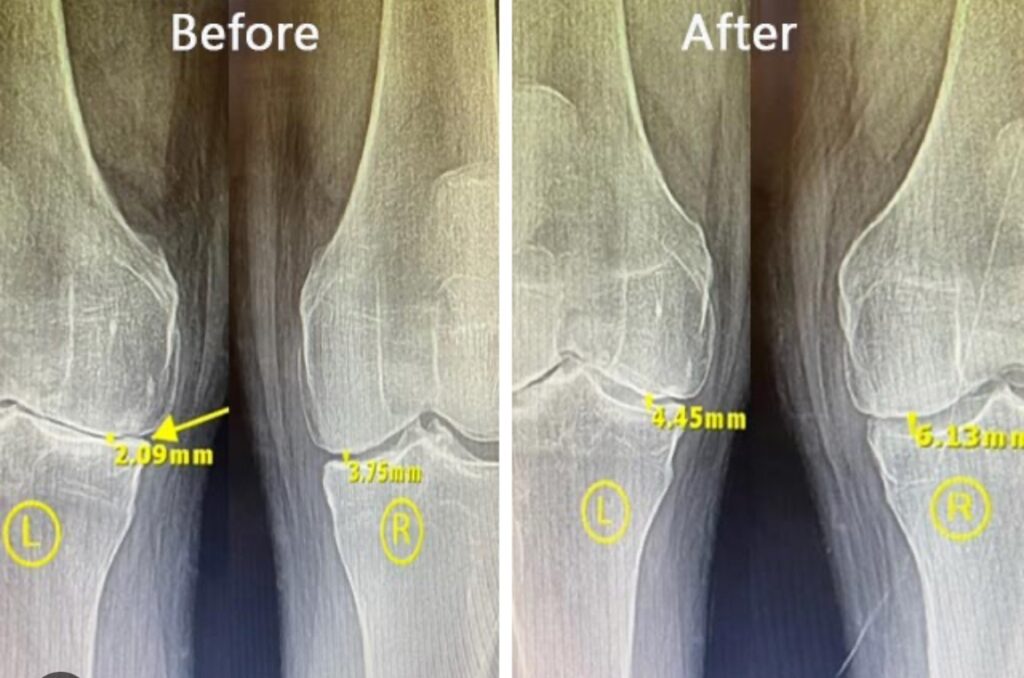

- Samara et al., 2022 — MRI confirmed cartilage regeneration following UC-MSC injection in moderate OA.

- ✅ Better cartilage quality in imaging studies